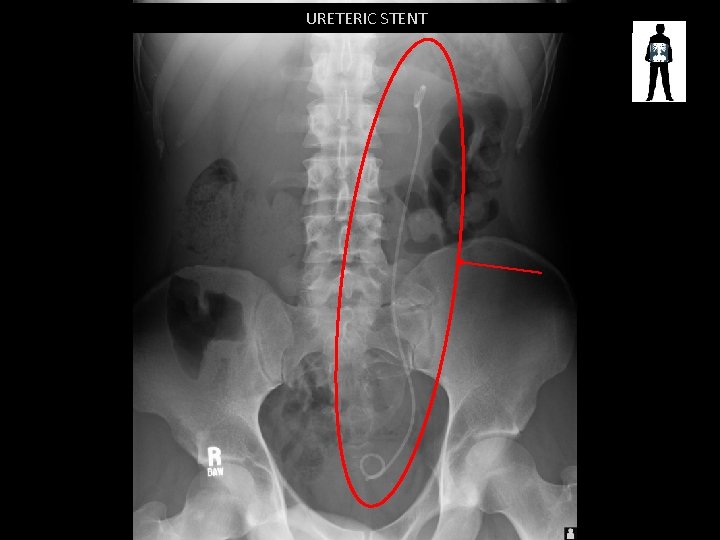

URETERIC STENT

URETERIC STENT • Installed antegrade (via nephrostomy) or retrograde (via retrograde ureterogram) • To release hydronephrosis caused by obstruction of the renal system – Stones – Pressure caused by disease